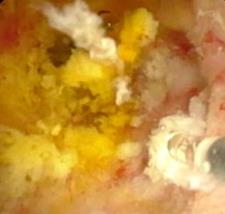

• 经皮经胆道镜激光消融术与光动力疗法治疗胆管黏液性囊性肿瘤的临床疗效及治疗技巧

摘要:目的 探讨经皮经胆道镜激光消融术与光动力疗法(PDT)治疗胆管黏液性囊性肿瘤的临床疗效及治疗技巧。方法 回顾性分析2018年1月-2023年12月该院消化内科收治的13例胆管黏液性囊性肿瘤患者的临床资料,采取经皮经胆道镜激光消融术、PDT治疗或两者联合治疗。观察患者手术相关情况、病灶情况、引流情况、术后6个月生存情况和并发症发生情况。结果 所有患者均顺利完成经皮经胆道镜激光消融、PDT或两者联合治疗,治疗成功率为100%。所有患者术后体温恢复正常。7例患者术后1周内黄疸明显减退,其余6例黄疸虽然未明显减退,但血清总胆红素有所下降或保持稳定。所有患者术后1周内,胆管各分支新生物减少,病灶明显缩小。术后早期(30 d内),所有患者引流管均保持通畅,未发生因肿瘤组织脱落或坏死物堵塞所导致的急性堵管事件。术后引流管留置时间平均为4.2个月。术后6个月,无死亡病例,术后6个月生存率为100%。未发生胆道穿孔和大出血等严重并发症。结论 经皮经胆道镜激光消融术联合PDT治疗胆管黏液性囊性肿瘤,可以缩小病灶范围,缓解胆道梗阻,提高患者生活质量,且并发症少。值得临床推广应用。